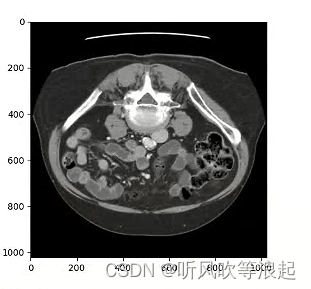

打印:

![]()

如下:不仅是2d,经过windowing方法对比度也好了很多